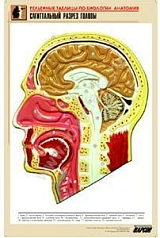

Комплект включает в себя 21 таблицу следующего содержания:

4. Сагиттальные разрез головы;